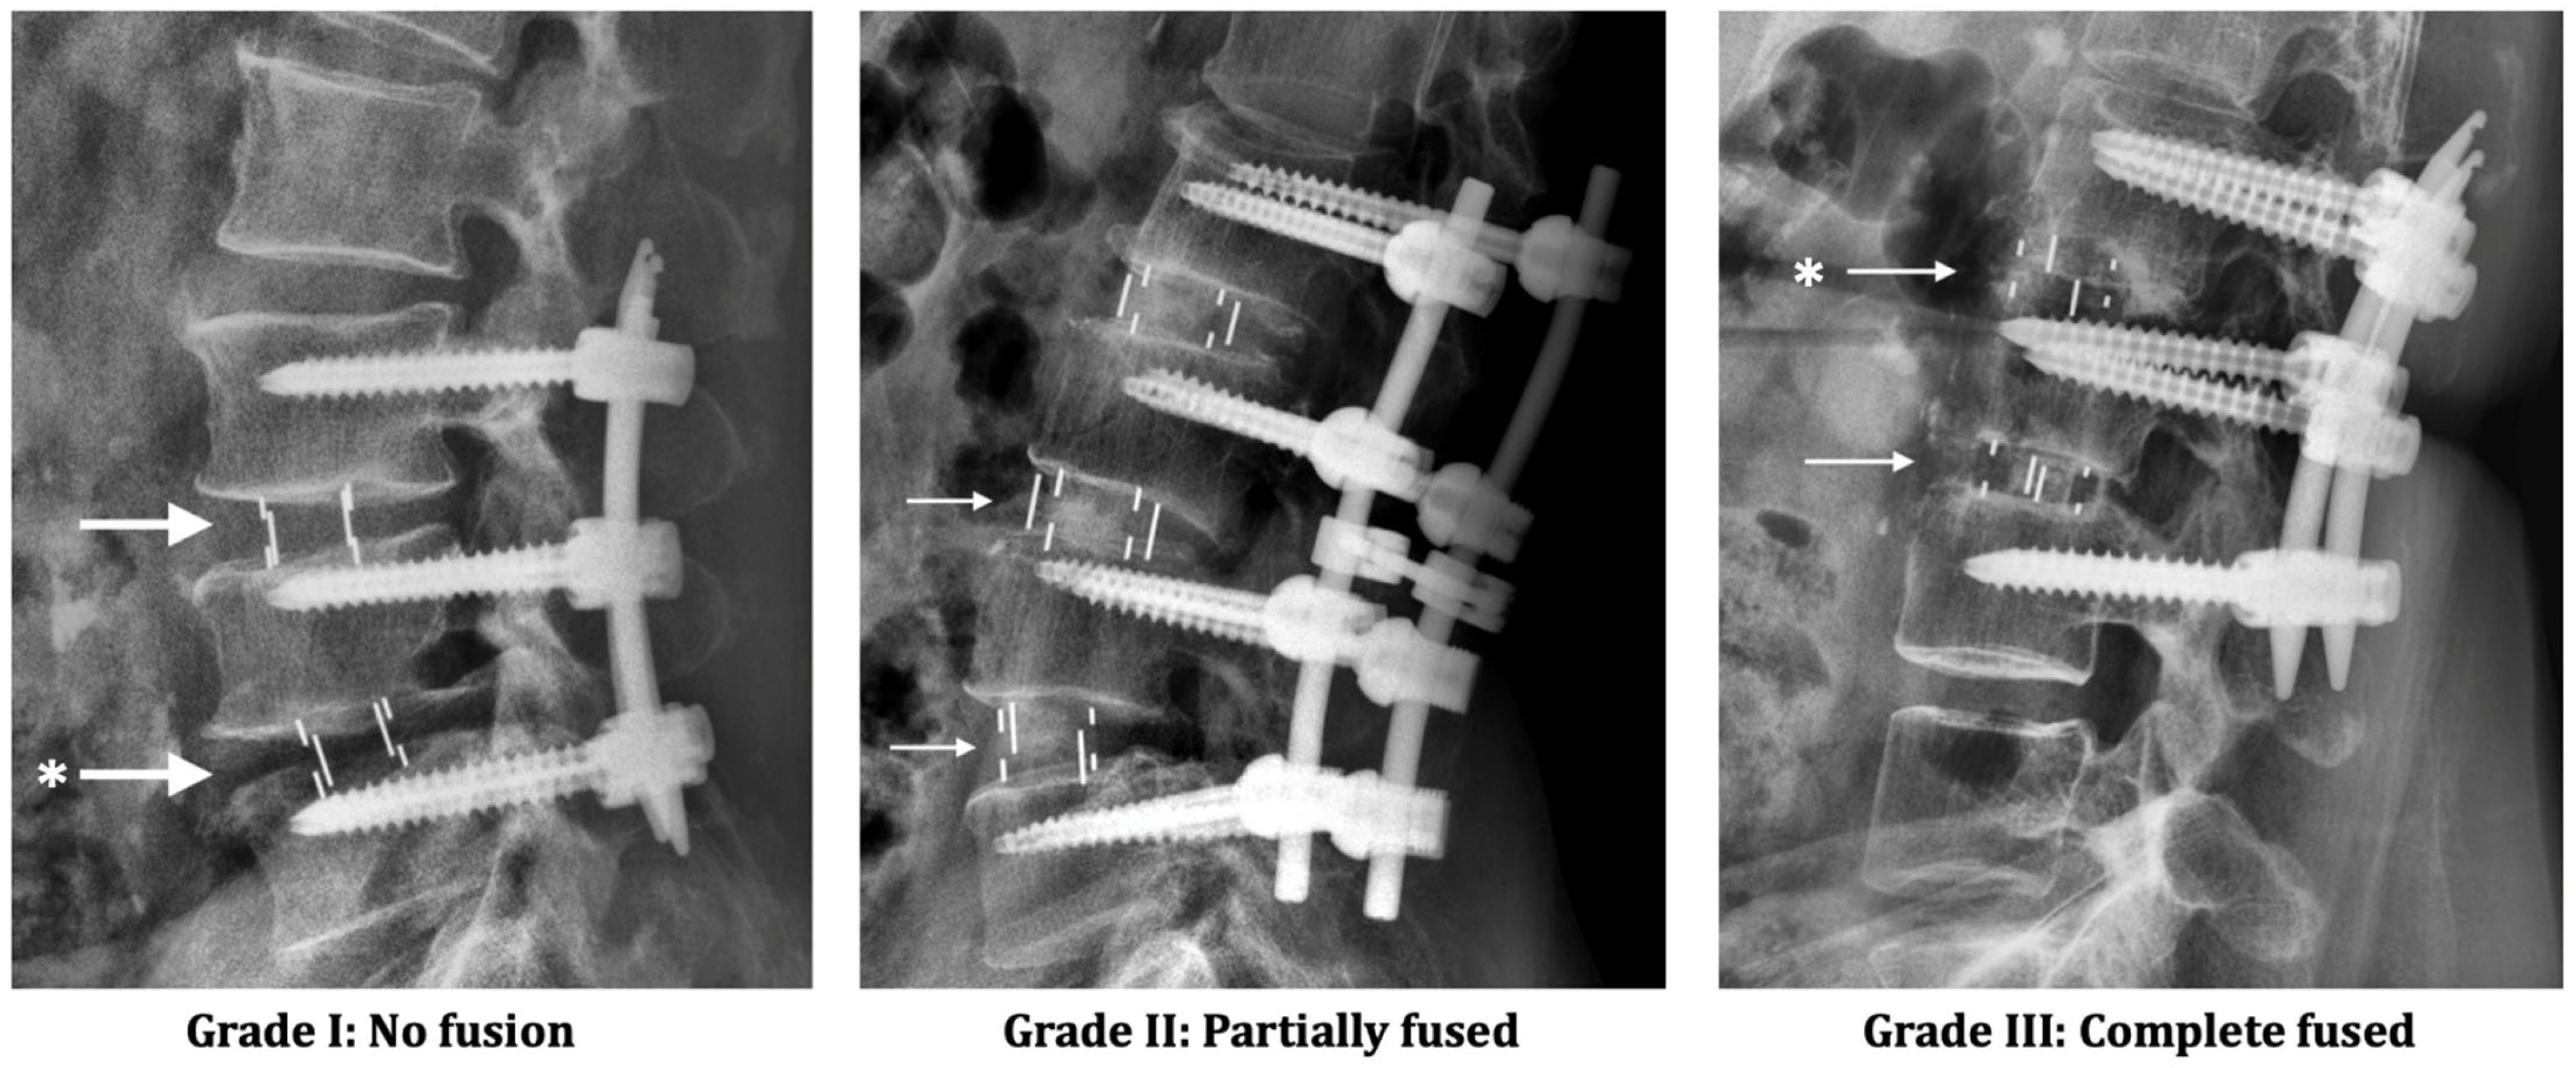

| Fusion status | 0.72 | |||

| Grade I | 0 (0%) | 0 (0%) | 0 (0%) | |

| Grade II | 4 (13%) | 5 (19%) | 9 (16%) | |

| Grade III | 26 (87%) | 22 (71%) | 48 (84%) | |